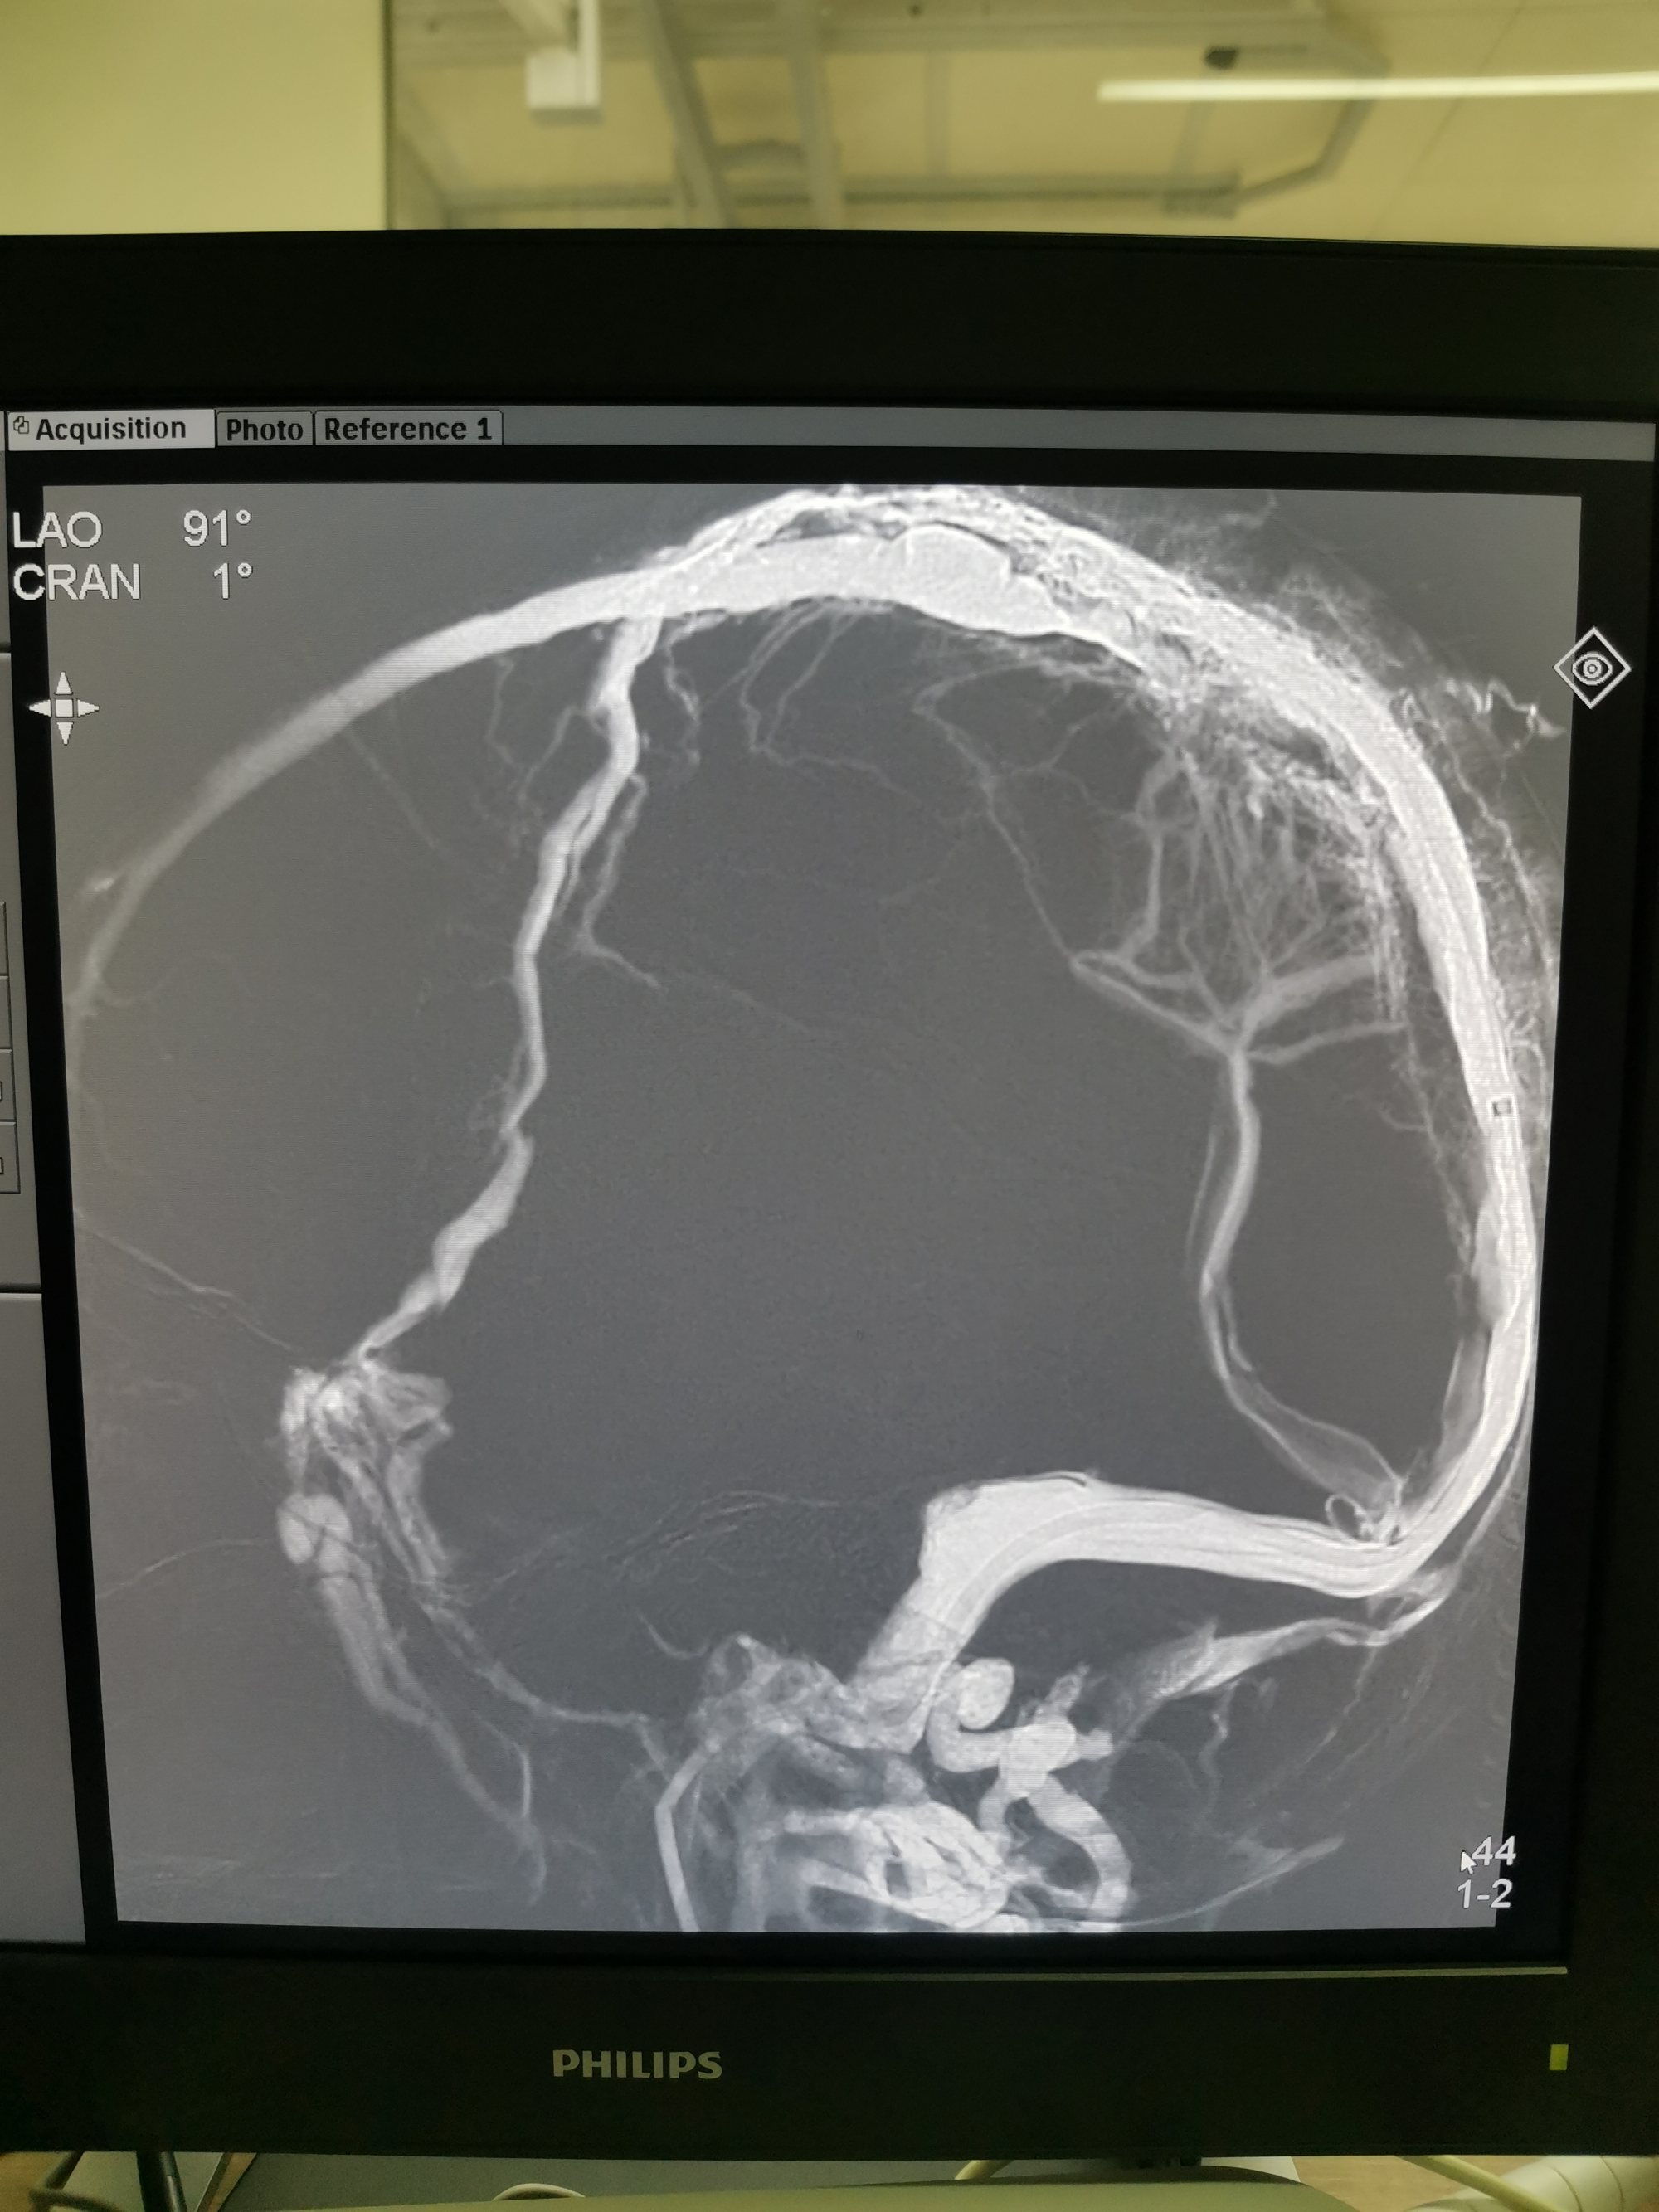

取栓后矢状窦血流恢复通畅。

最后关头动脉短鞘竟意外从股动脉内脱出,无法行动脉造影,遗憾!只能行静脉手推造影,矢状窦恢复正向血流。

矢状窦仍有部分血栓,局部有狭窄,术后给予抗凝抗血小板治疗。术后患者意识清醒,肢体运动同术前,语言功能正常。